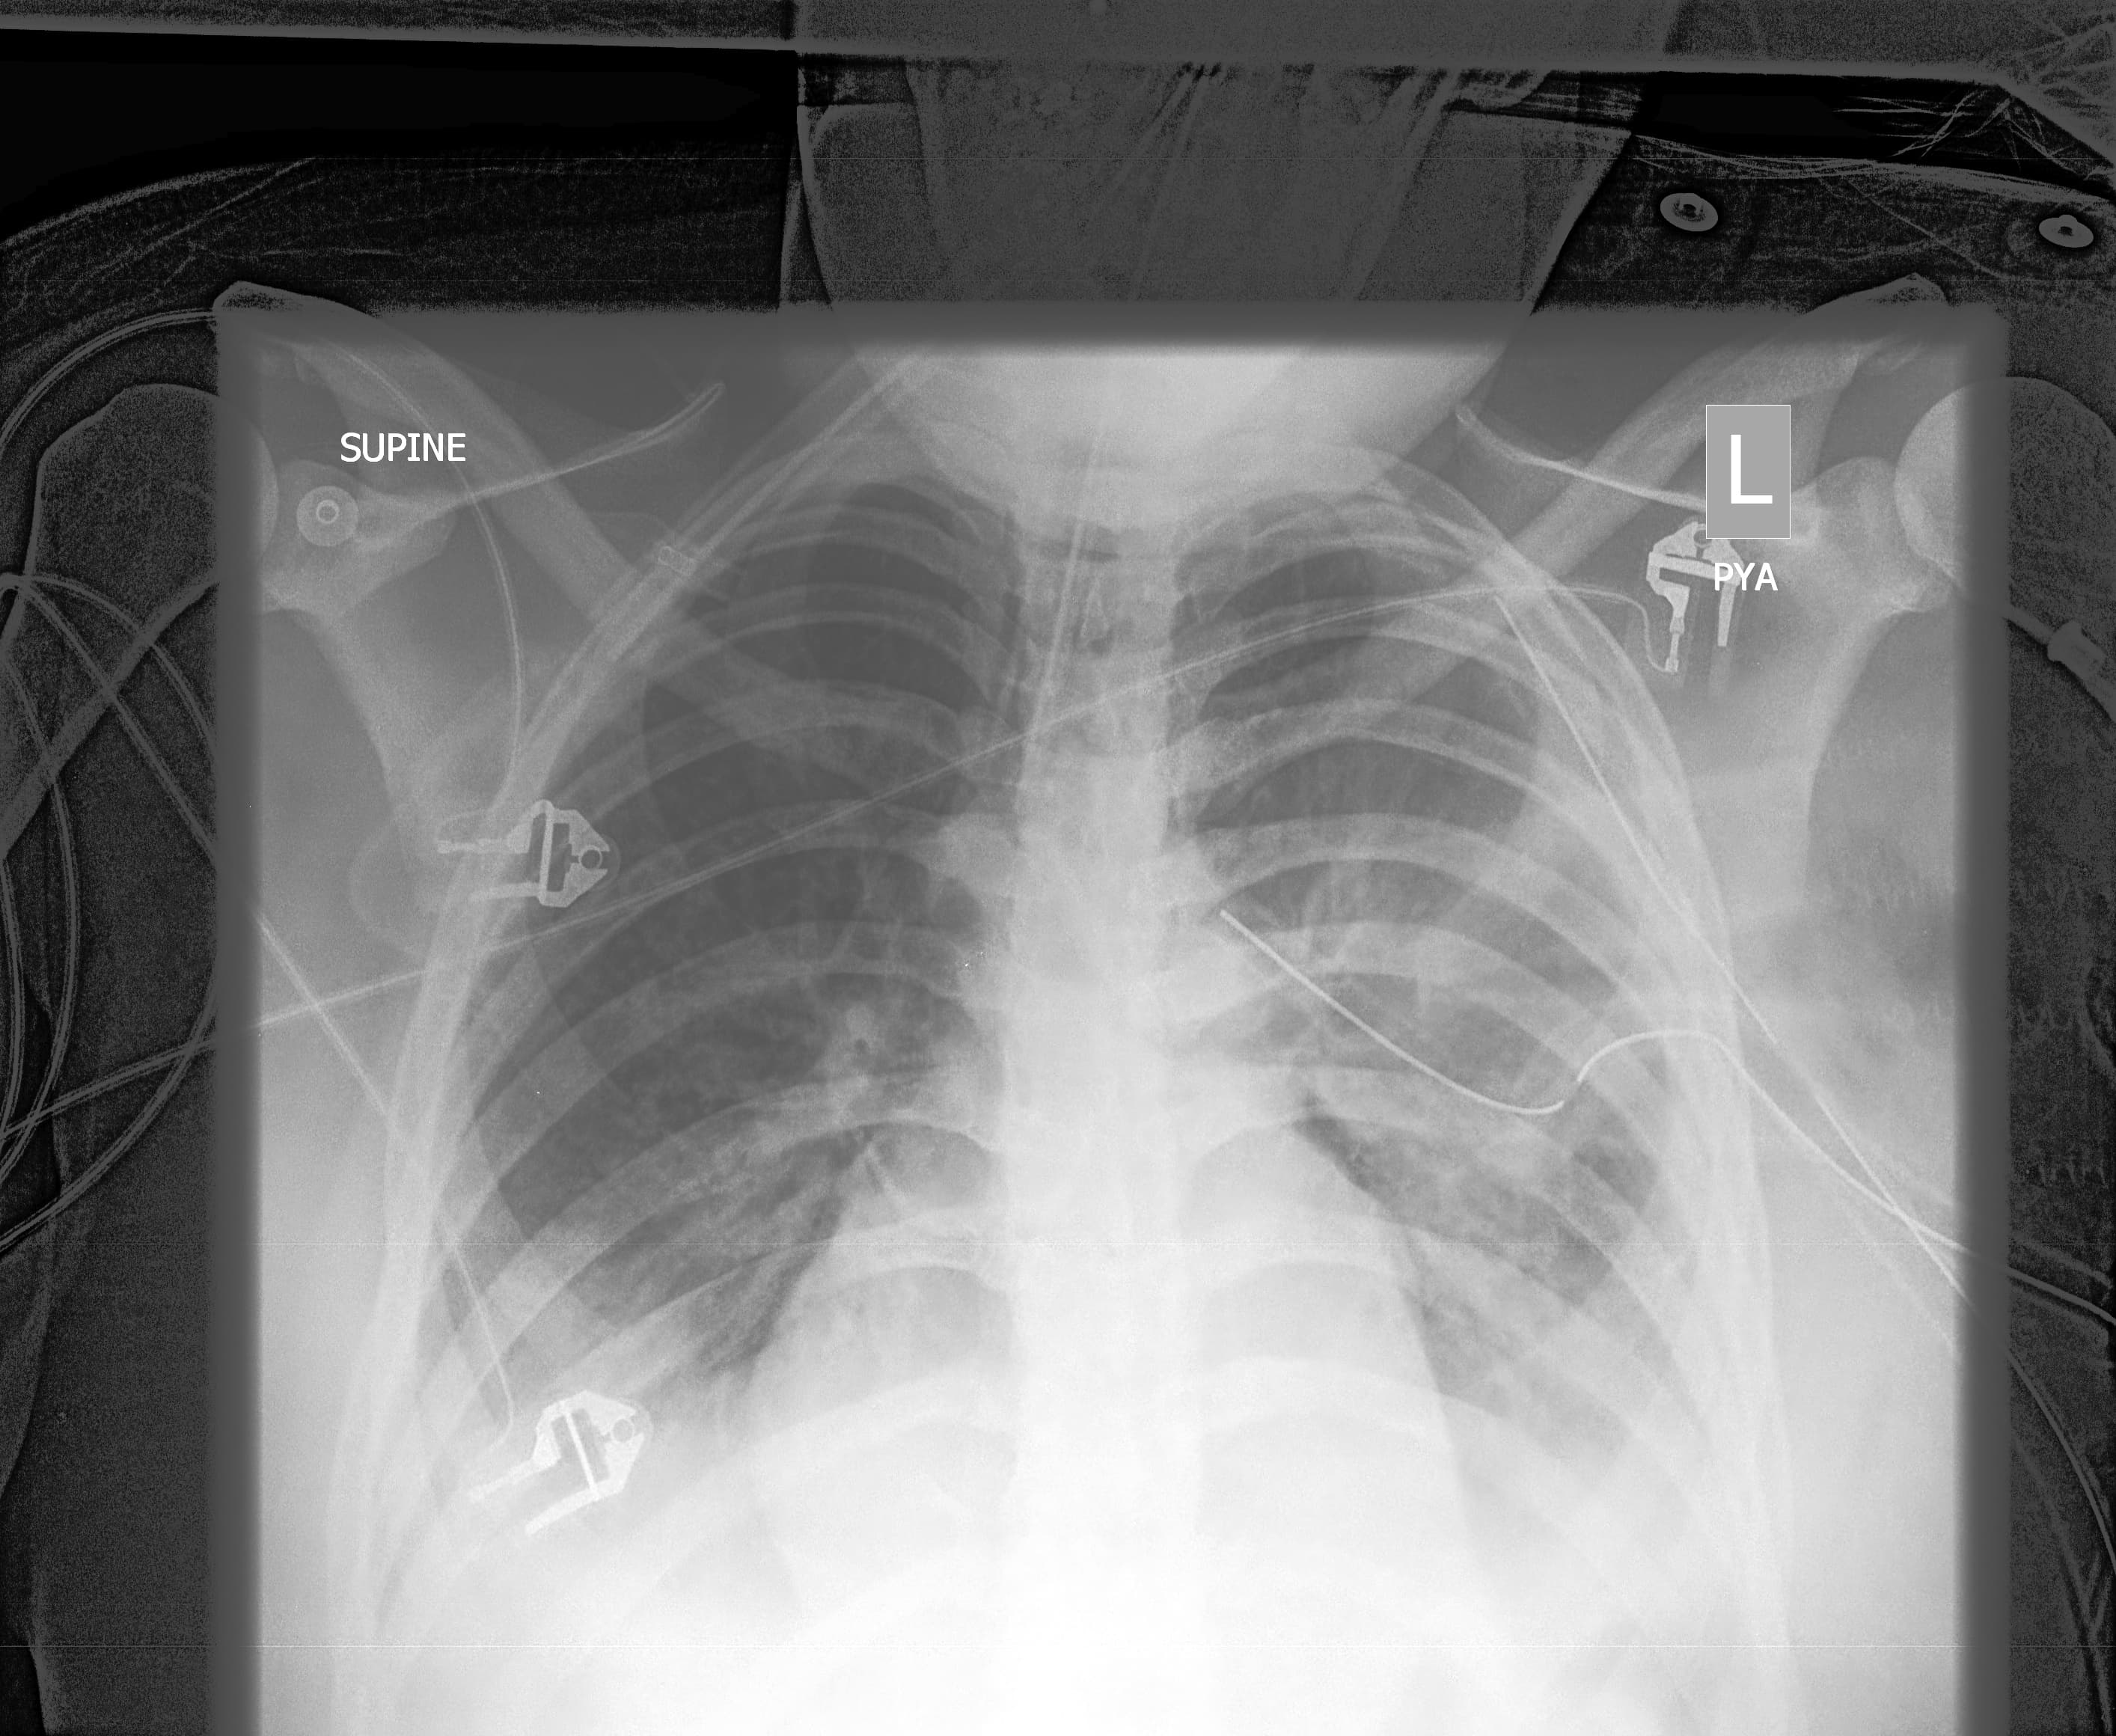

모델 예측 결과

Input X-ray

Prediction + Grad-CAM

최종 학습된 모델에 X-ray 이미지를 입력하여, 가장 높은 확률로 예측된 질환 결과를 시각화한 예시입니다.